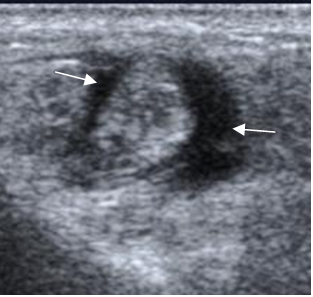

Fig 71. Tenosinovitis.

Ecografía axial. Tendones peroneos engrosados y rodeados por líquido, por tenosinovitis.